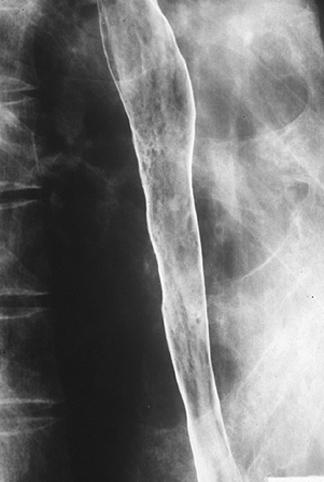

疾病(病理主体)的分类恶性上皮肿瘤/扁平上皮癌

部位(按器官分)食道/中

检查方法X线

肿瘤的肉眼分类0型(表在型)/IIc型(IIc+IIb)

肿瘤最大直径40以上